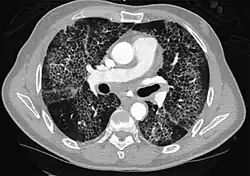

CT image showing crazy paving pattern of ground-glass opacities in both lungs.

The crazy paving pattern may occur when there is both interlobular and intralobular widening. This sometimes resembles a road paved with irregular bricks or tiles. It is typically diffuse, involving larger areas of one or multiple lobes. There are a variety of potential causes, including Pneumocystis pneumonia, late-stage adenocarcinoma, pulmonary edema, some types of idiopathic interstitial pneumonias, diffuse alveolar hemorrhage, sarcoidosis, and pulmonary alveolar proteinosis.[6] COVID-19 has also been shown to occasionally cause GGOs with a crazy paving pattern.[11]

Several studies have described a pattern among initial, intermediate, and hospital discharge imaging findings in the disease course of COVID-19. Most commonly, initial CT imaging reveals bilateral GGOs at the periphery of the lungs. During initial stages, this is most often found in the lower lobes, although involvement of the upper lobes and right middle lobe has also been reported early in the disease course.[16][18] This is in contrast to the two similar coronaviruses, SARS and MERS, which more commonly involve only one lung on initial imaging.[19][20] As the COVID-19 infection progresses, GGOs typically become more diffuse and often progress to consolidation.[11][18] This is sometimes accompanied by the development of a crazy paving pattern and interlobular septal thickening.[18] In many cases the most severe pulmonary CT abnormalities occurred within 2 weeks after symptoms began.[17] At this point, many individuals begin showing resolution of consolidation and GGOs as symptoms improve. However, some patients have worsening symptoms and imaging findings, with further increase in septal thickening, GGOs, and consolidation. These patients may develop lung "white-out" with progression to acute respiratory distress syndrome (ARDS) requiring treatment escalation.[17][21]